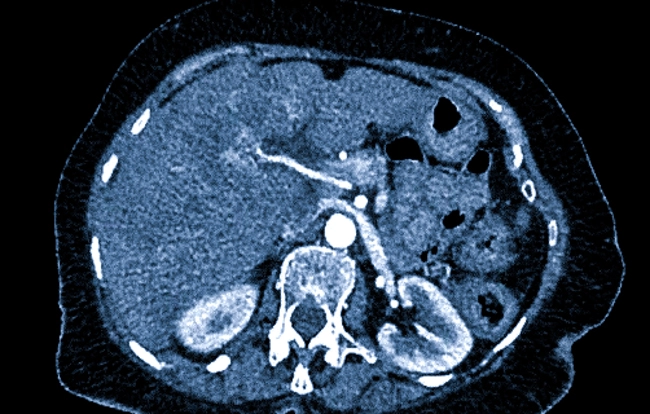

КТ печени — это процедура, при которой с помощью компьютерной томографии получают трехмерные изображения этого органа. Такой метод позволяет тщательно оценить структуру печени, выявить наличие патологий, определить размеры и расположение опухолей, а также оценить состояние сосудов и окружающих тканей.

- Диагностика опухолей: выявление первичных и вторичных злокачественных новообразований.

- Обнаружение кист, абсцессов или гематом.

- Оценка состояния печени при хронических заболеваниях: цирроз, гепатит.

- Выявление метастазов в печени при раковых опухолях других органов.